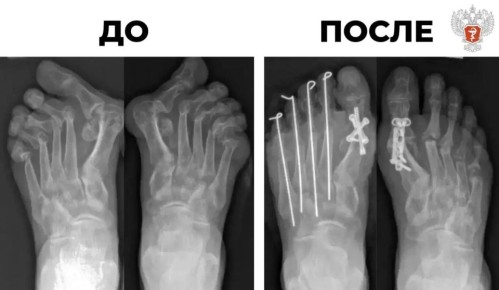

Пациентка поступила в Новосибирский НИИ травматологии и ортопедии им. Я. Л. Цивьяна Минздрава России с сильной деформацией десяти пальцев на ногах, вызванной ревматоидным артритом.В последнее время боль и слабость в суставах ног постепенно усиливались...